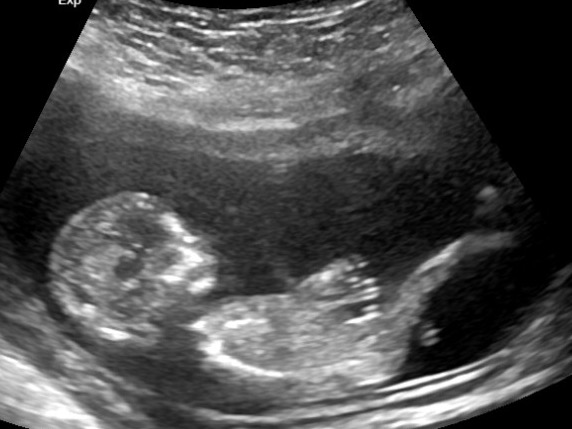

Hi Everyone! I'm just wondering if anyone can provide any insight on whether you think this Ultrasound at 14 weeks is a boy or girl. Thank you!! :)Attachment 32026Attachment 32027

Do you have a potty shot?

I'm not sure if this is a potty shot. To be honest, all I know is that I'm looking at two legs. What do you think?

Definitely boy [emoji170]! In the previous pic of the potty shot, you can see a scrotum.